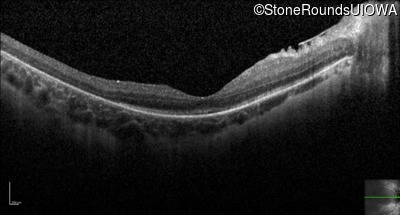

Optical Coherence Tomography - Left - 10/160 -1 sc

Exemplar / OCT Stack